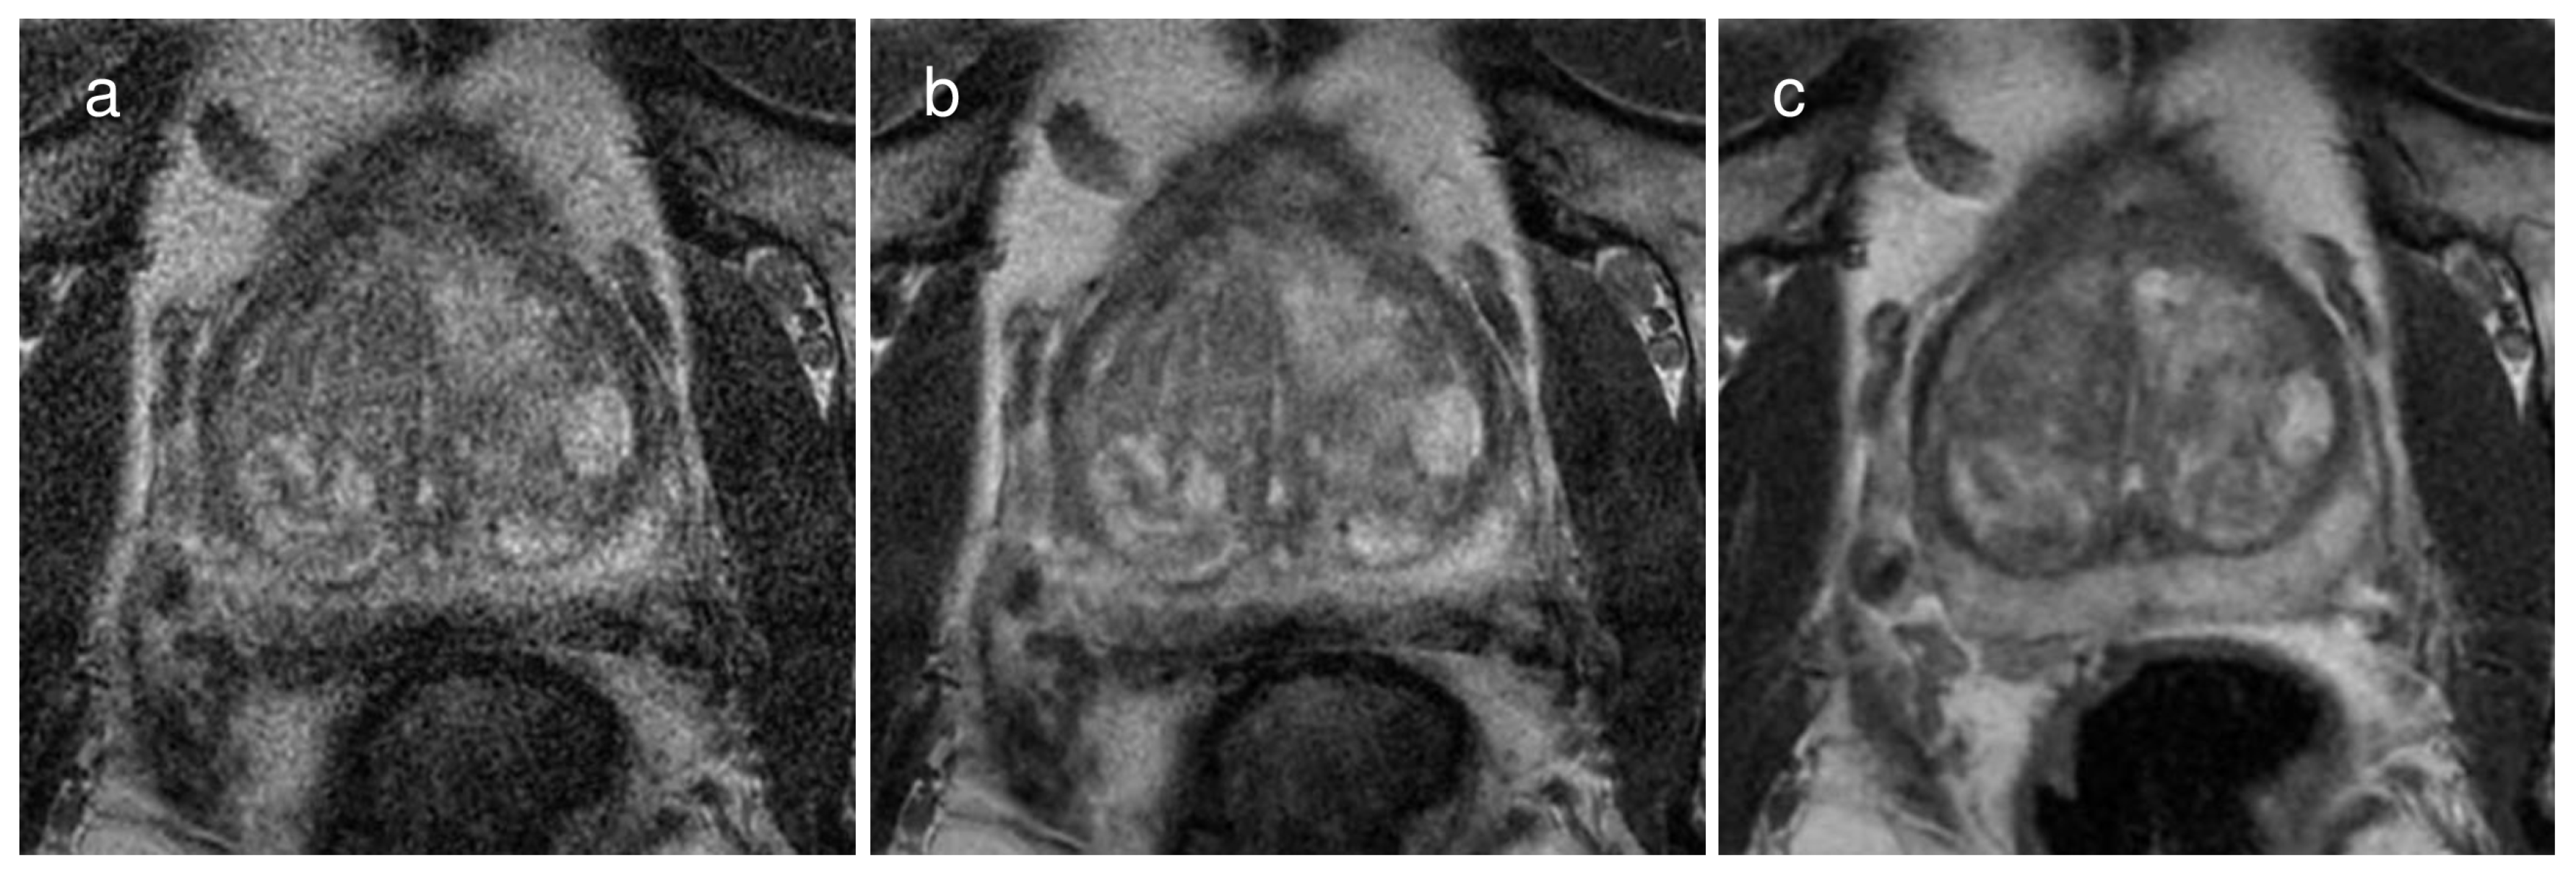

Figure 3.

A representative case of a 67-year-old man with a Gleason score of 6 demonstrating the image quality of each image dataset on (a) a 2 mm thin-slice T2WI without deep learning reconstruction (DLR), (b) the same T2WI with DLR, and (c) conventional T2WI with 3 mm slice thickness. The subjective image quality score was the best on conventional T2WI, followed by the thin-slice T2WI with DLR and the same T2WI without DLR. Specifically, the scores were 5, 4, and 3, respectively, for reviewer 1 and 4, 3, and 2, respectively, for reviewer 2.